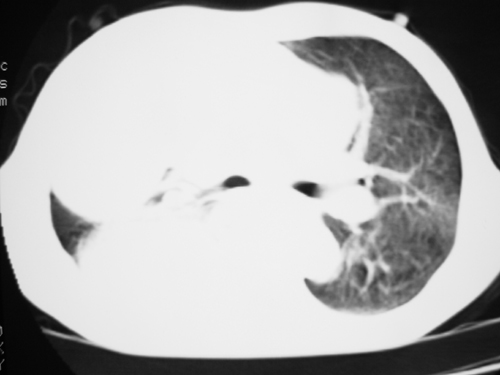

以下是引用yangyudong333在2008-4-29 5:46:00的发言:[br]1左上叶结节呈分叶状,边缘毛刺,考虑肺癌并纵隔淋巴结转移可能性大,结核待排,[br] [br]2右侧多发包裹性胸腔积液

以下是引用zsl6918在2008-4-29 9:15:00的发言:[br]右侧包裹性积液穿刺术后改变,肺内多发结节不除外转移可能。建议查胸水,问病史。